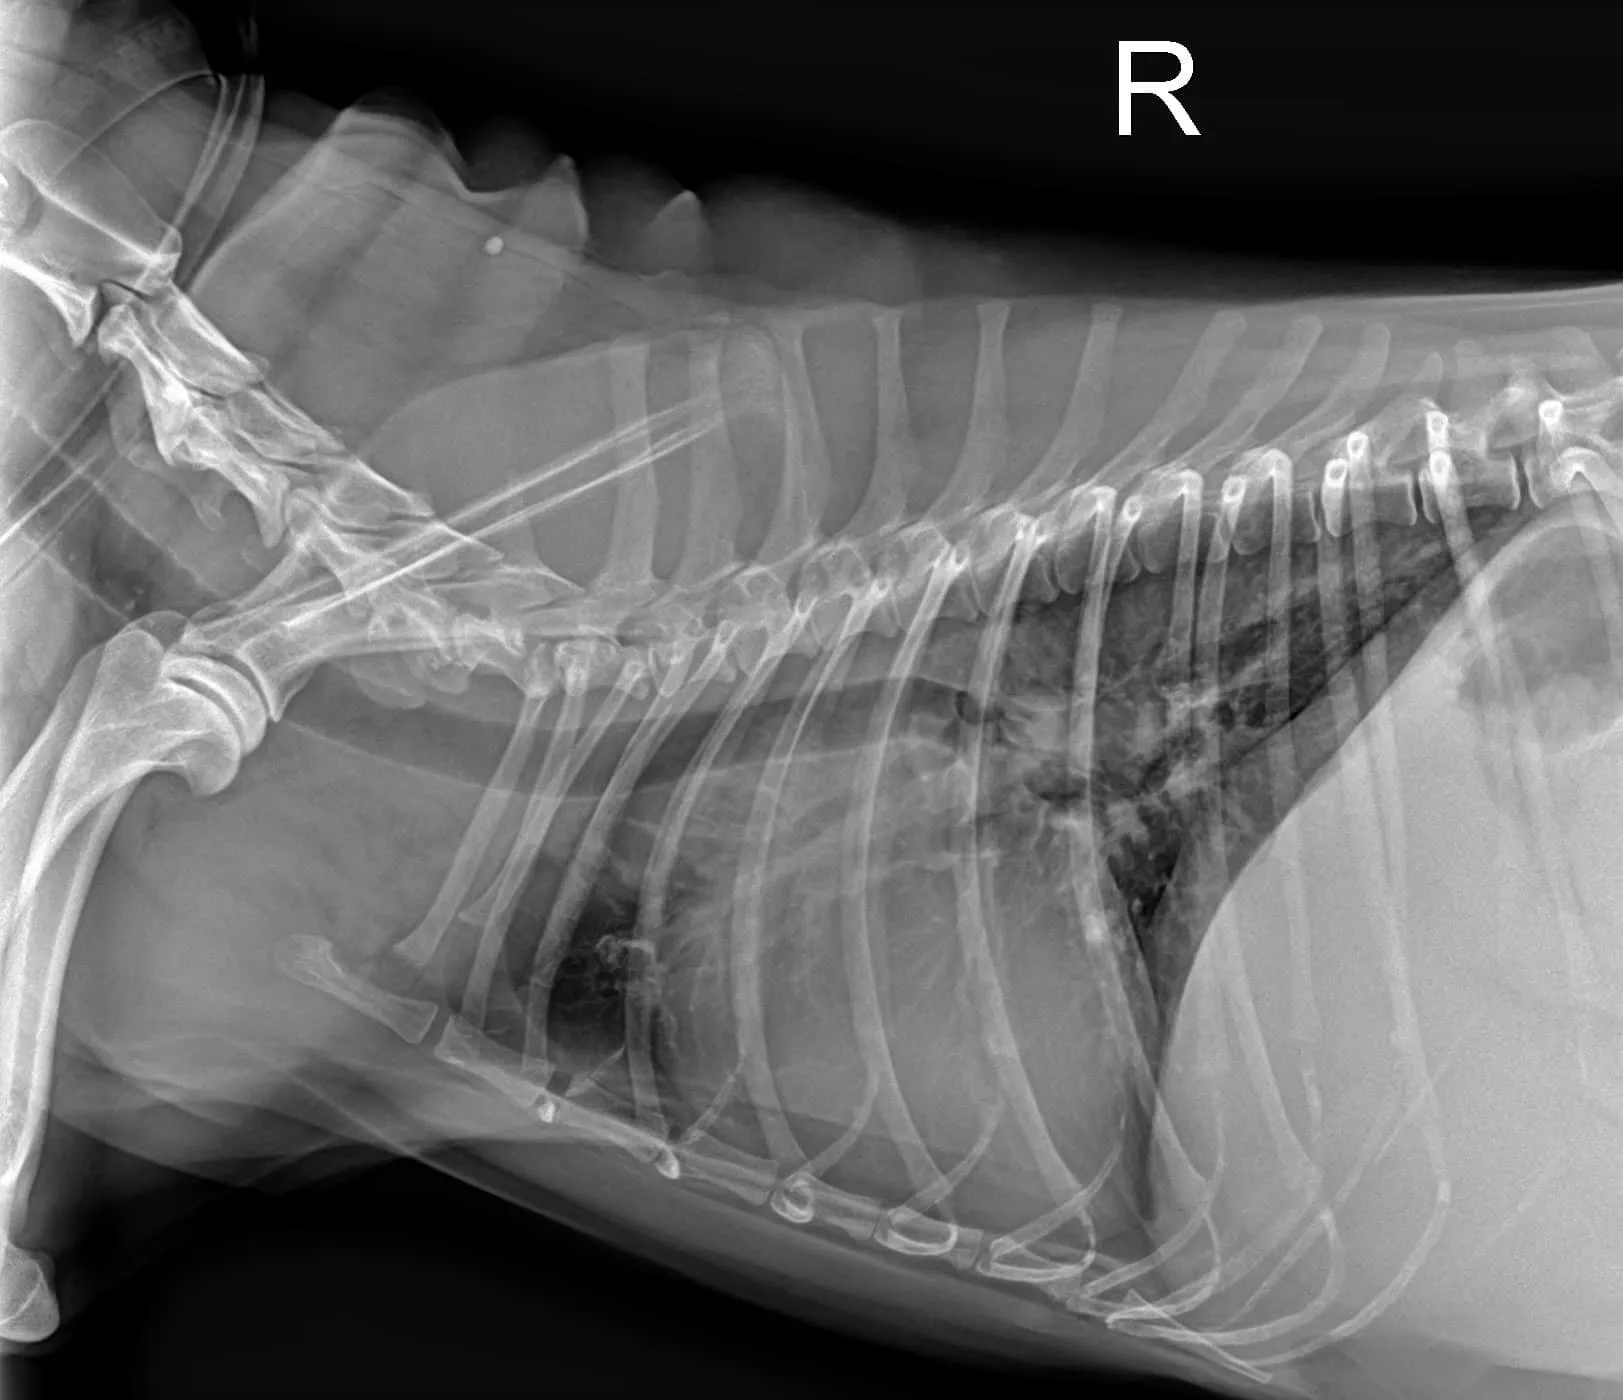

病例分享 毛孩的臨床症狀 1. 突然變很喘,伴隨間斷性劇烈咳嗽。 2. 精神食慾正常,於友院服用止咳藥物後,無顯著改善。 3. 腹部異常膨脹,於

當遇到毛孩有呼吸急促、會喘、咳嗽、呼吸困難等狀況時,安可的醫師腦海裡其實已經開始思考所有可能的原因,例如: 心臟問題、肺臟問題、胸膜腔壓迫性疾病、疼痛,抑或是其他生理性等問題,都一一跑過